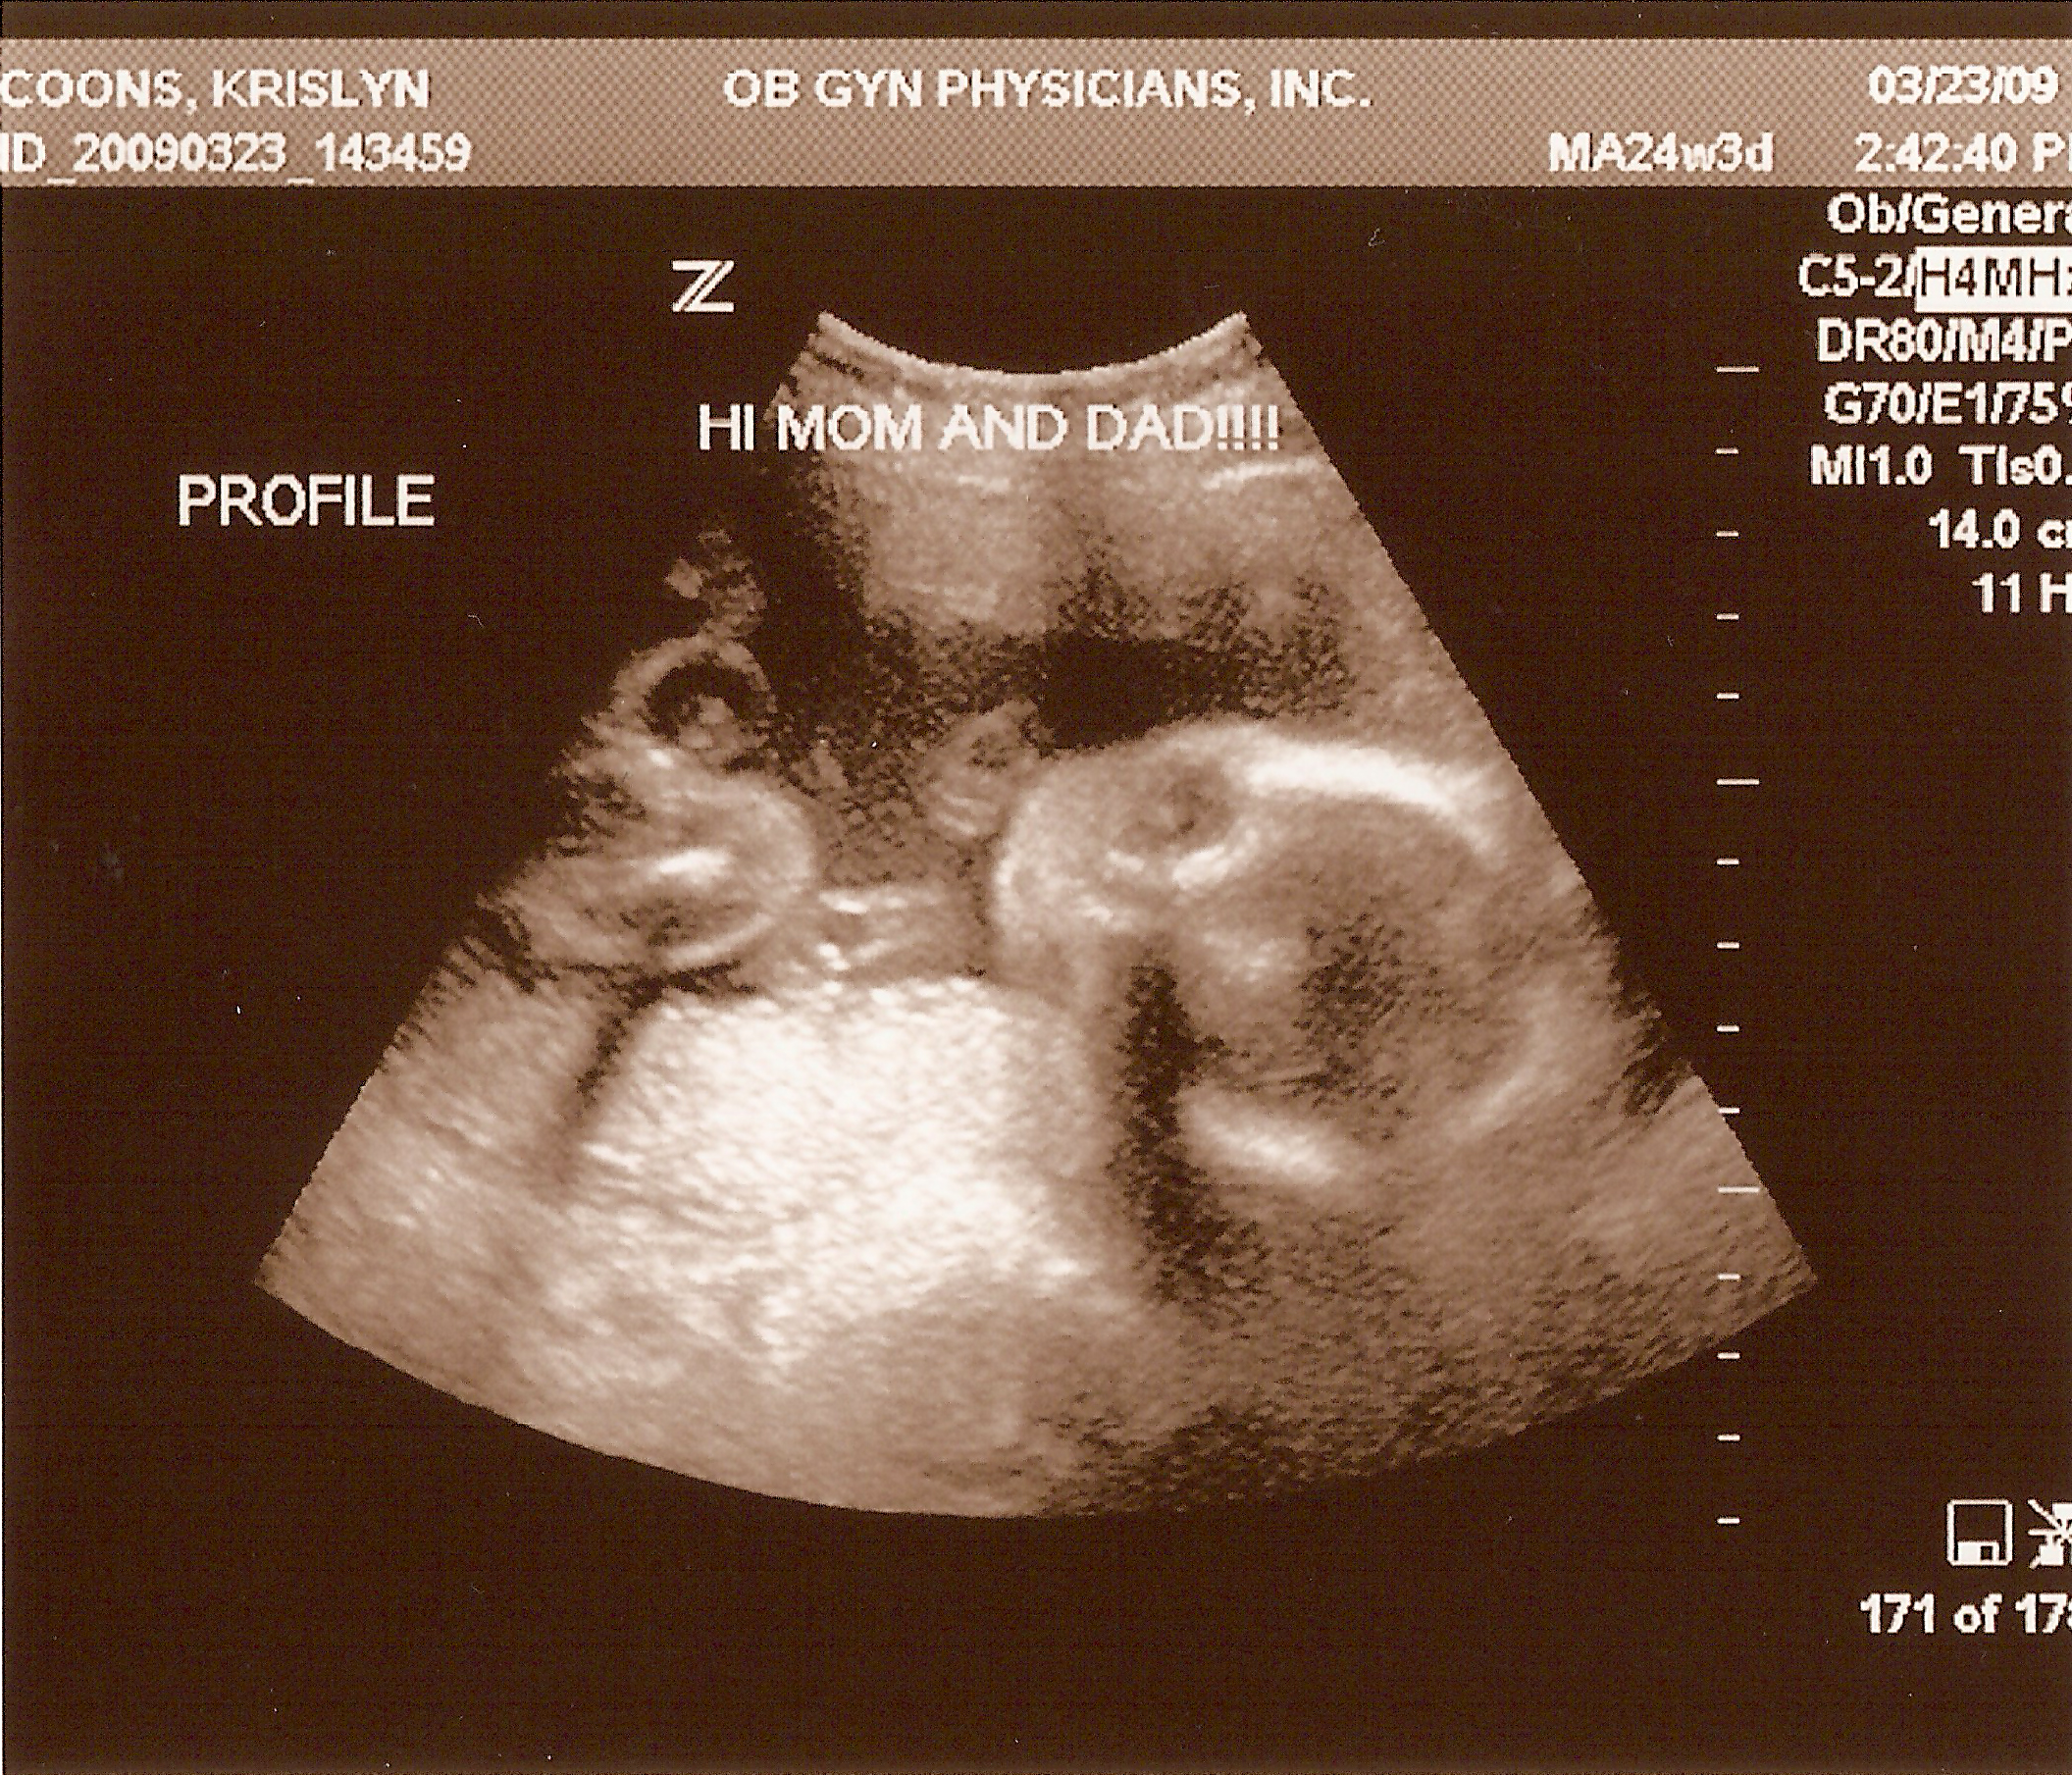

3.23.2009

Second ultrasound! Baby is doing well and all measurements checked out--weighing in around 1.7 pounds. No abnormalities on the PentaScan, so no need for an amnio. And Krislyn is really starting to show now!

24 weeks